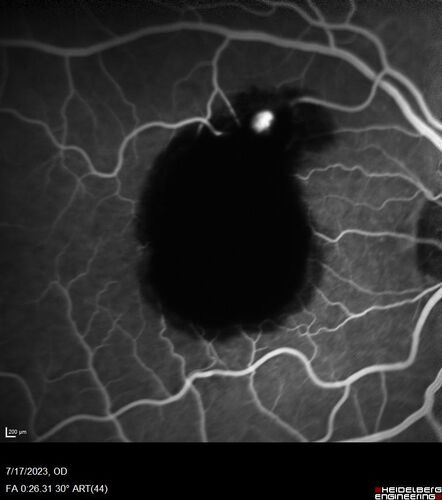

Retinal Arterial Macroaneurysm with pre-retinal hemorrhage

72 year old female who takes Xarelto had sudden vision loss while moving heavy furniture.  VA was 20/200.  The lesion has preretinal blood but later rebled with subretinal blood, was lasered and the final vision was not very good but the patient was lost to follow-up at 3 months